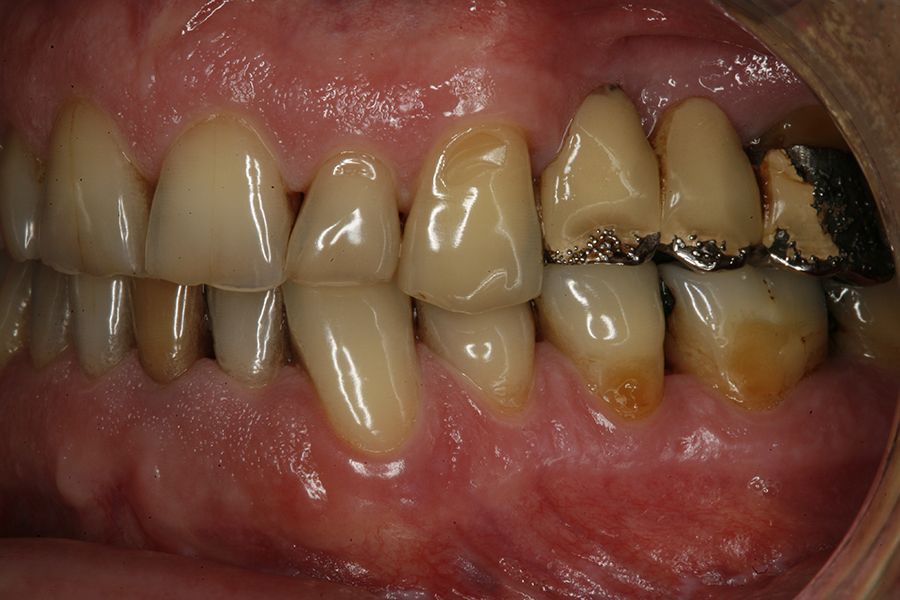

Material and method: We retrospectively recruited patients who attended our dental clinic with problems in different implant rehabilitations of an eminently mechanical nature (fracture of ceramics, prostheses, or components as well as implants) who underwent respiratory polygraphy to reveal the possible presence of OSA. In those cases where this disorder was found to be present, we selected patients with moderate-severe OSA (apnea- hypopnea index (AHI) ≥ 20) to analyze the different adverse events that occurred according to the severity of the sleep disorder recorded.

Results: Twenty-two patients who met the previously established inclusion criteria were recruited. Adverse events were identified in all patients in their implant restorations, these complications being fracture of the prosthesis ceramic (63.6%), structural fracture of the prosthesis in 18.2% of the cases (structure itself or resin coating in hybrids) and fractures or cracks in the implants in 18.2% of the cases. The mean AHI (apnea-hypopnea index) of all patients was 33.29 (+/- 18.90; range 20-110). If we analyze the presence of adverse events in the prostheses according to the AHI, we find that most adverse events are concentrated in the higher AHI ranges. A therapeutic approach with CPAP (continuous pressurized airway oxygen delivery device) combined with a mandibular advancement device (DIA) was used in two patients, the rest only DIA. With treatment completed, patients went from a mean AHI of 33.29 (+/- 18.90) to a mean of 17.38 (+-10.37), these differences being statistically significant (p<0.001).

sleep disorders such as OSA and oral pathology, for example bruxism or fractures, of various rehabilitations, both on teeth and on implants, is widely documented today. This association has been demonstrated in several epidemiological studies over the years3-7, with our research group highlighting that the presence of dental wear in patients should prompt a thorough sleep analysis, as the degree of dental wear is directly related to OSA via the AHI (apnoea-hypopnoea index)9-11. This relationship is directly proportional, and it is confirmed that patients with more severe wear also exhibit a higher AHI, which is likewise associated with an increased incidence of fractures in enamel, dental roots, and prostheses. Mechanical events may,

in some cases, also affect implants, resulting in bone defects due to overload, and in extreme cases, leading to fracture of the implant itself.12-14. In the following clinical case series, we sought to retrospectively collect a group of patients who experienced adverse events in implant-supported prostheses associated with mechanical overload (fractures, loosening), to whom a subsequent polygraphic sleep study was performed, identifying those in whom these events could be related to the presence of OSA. The most severe cases identified (AHI ≥ 20) were analysed to obtain data correlating both events (OSA and mechanical complications).